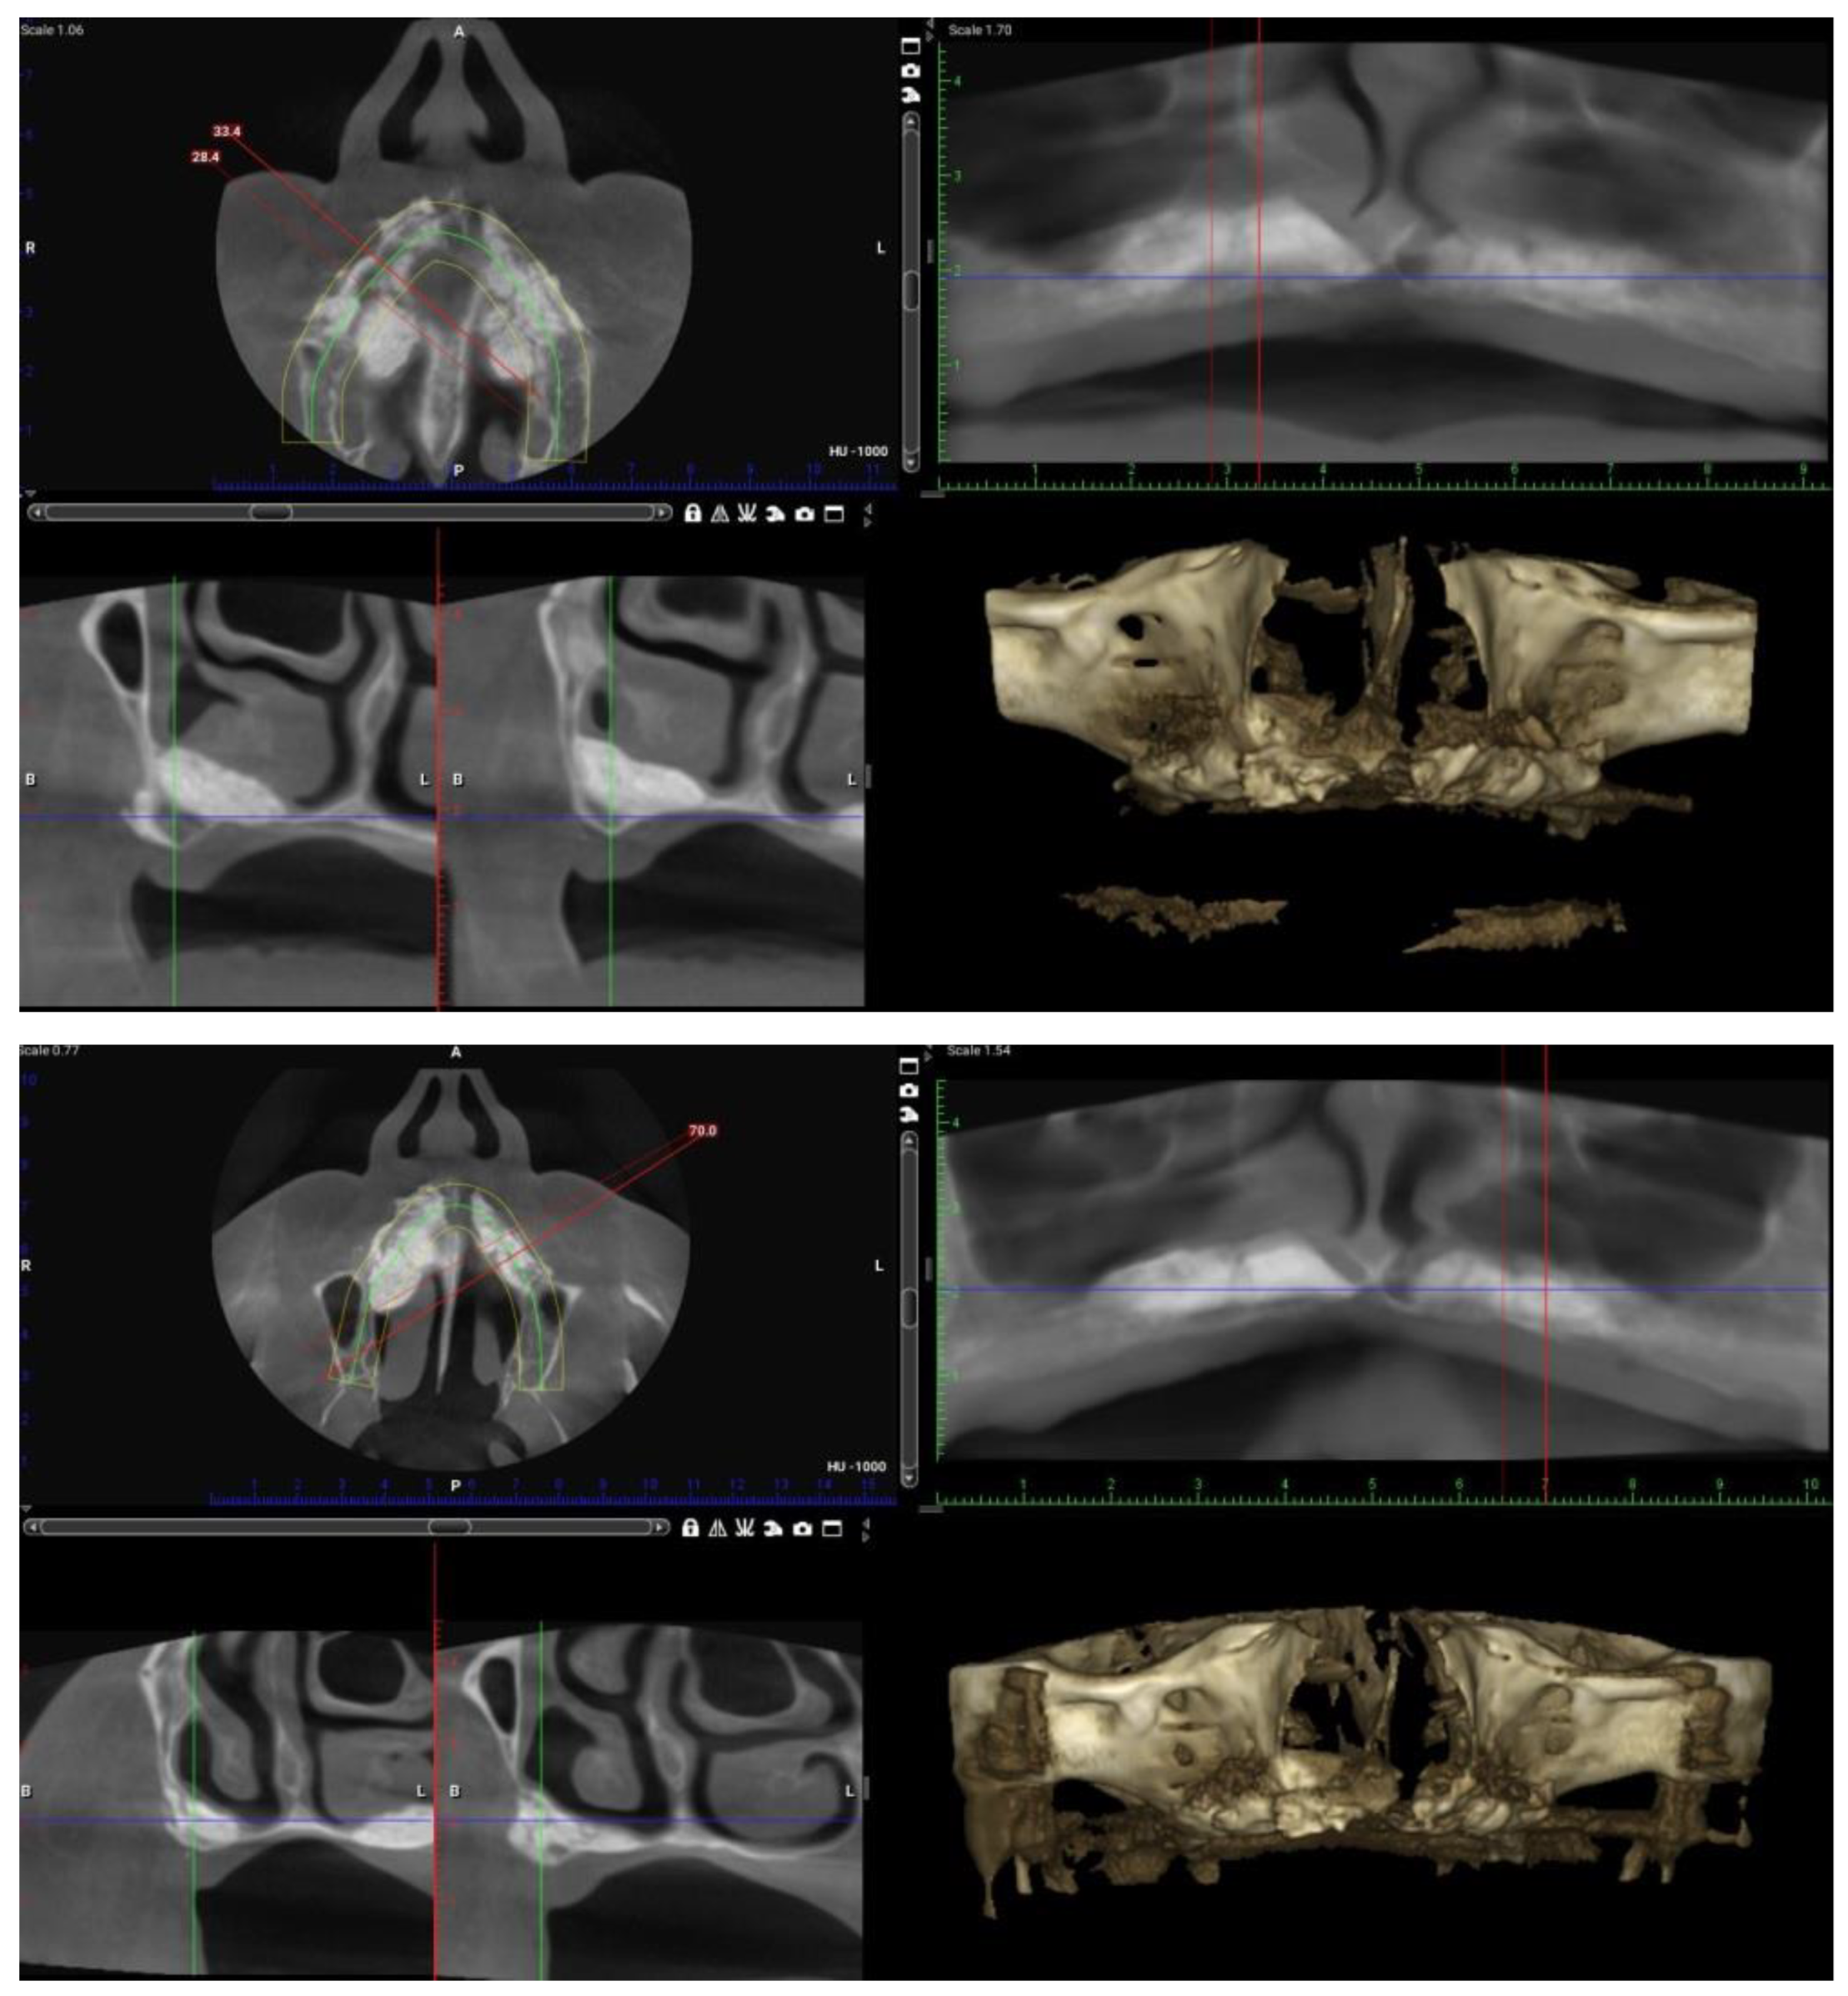

2. Case Report